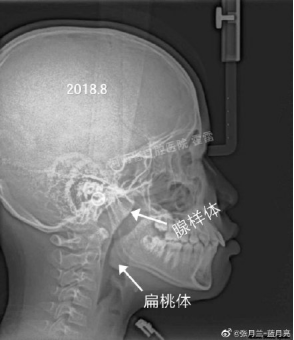

之前,郑州大学口腔医学院正畸教研室的张主任在微博发了一组图片:

一名11岁的男孩因为“嘴巴往外突出”,想要做矫正。

经过医生询问,发现男孩有晚上“张口睡觉”的习惯,进一步拍片检查后发现:男孩有严重的鼻腔气道阻塞。

而这,才是造成男孩“嘴突”的真正原因。

在医生的建议下,男孩做了扁桃体和腺样体切除手术,一年后再复查,孩子的“嘴突”现象慢慢不见了。